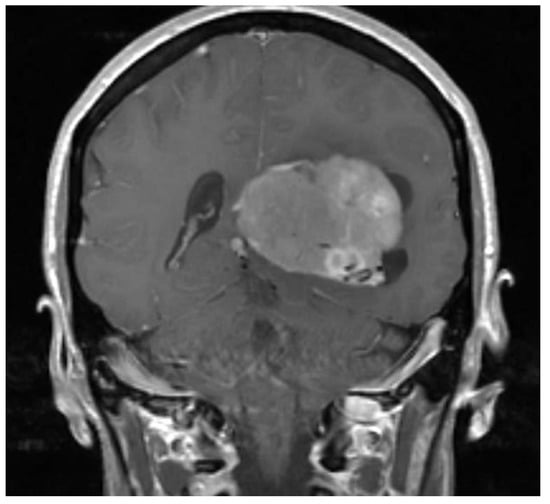

2. Case Presentation